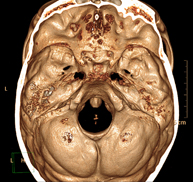

- Neurorradiología- TC Cráneo Prueba radiológica que consiste en obtener imágenes del cráneo de alta definición anatómica (tronco cerebral, cerebelo, cerebro, calota craneal, etc.), mediante el empleo de un equipo de TC (Tomografía Computarizada).Indicaciones: traumatismos, cefalea, trastornos de la memoria, pérdida de fuerza súbita en una extremidad o mitad del cuerpo. Prueba radiológica que consiste en obtener imágenes del cráneo de alta definición anatómica (tronco cerebral, cerebelo, cerebro, calota craneal, etc.), mediante el empleo de un equipo de TC (Tomografía Computarizada).Indicaciones: traumatismos, cefalea, trastornos de la memoria, pérdida de fuerza súbita en una extremidad o mitad del cuerpo.